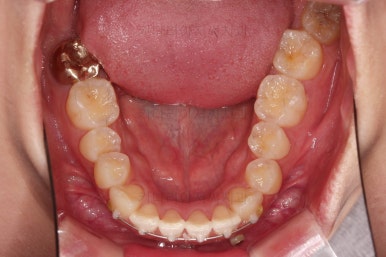

초진 시 입안의 모습입니다.

어금니 쪽은 약간 삐뚤긴 하지만 꼭 교정해야 할 정도는 아니고, 불편감 없이 비교적 잘 맞물리는 상태였습니다.

다만, 앞니ㅉㄱ이 공간이 부족해서 중간 치아들이 많이 회전되어있는데, 이를 환자분들의 표현에 따르면 "나비치아" 라고 부릅니다.

위아래 중간 앞니가 모두 나비치아처럼 되어있고요.

윗니가 아랫니보다 앞쪽으로 나와 있는 모습에 아래앞니가 윗니쪽으로 깊숙이 올라간 "과개교합" 양상을 보였습니다.